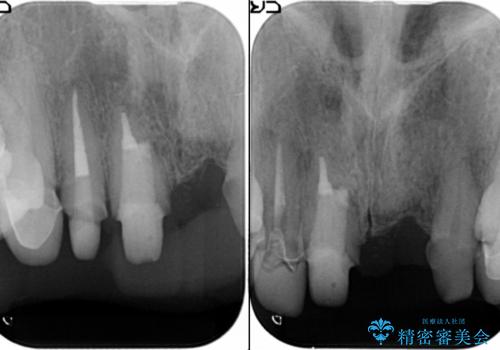

[ セラミック治療 ] 歯ぐきの際の黒ずみを改善したい

- 歯ぐきとセラミックの間の黒ずみが目立つので、きれいに治してほしい。と希望され来院されました。

歯ぐきの位置が変化しクラウン下の歯が見えるようになってしまったことで、審美障害が生じている状態です。

クラウンマージンの再設定を行うことで、黒ずんだ部分を再度覆い、審美障害を改善します。